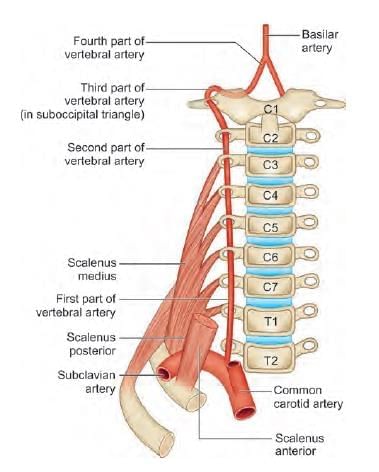

Third part of vertebral artery is related to which of the following marked region in the following diagram? (INI-CET Nov 2021)